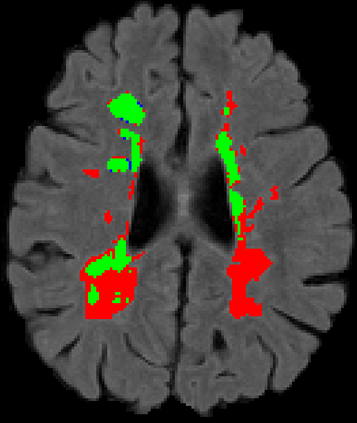

Recently, segmentation methods based on Convolutional Neural Networks (CNNs) showed promising performance in automatic Multiple Sclerosis (MS) lesions segmentation. These techniques have even outperformed human experts in controlled evaluation conditions such as Longitudinal MS Lesion Segmentation Challenge (ISBI Challenge). However state-of-the-art approaches trained to perform well on highly-controlled datasets fail to generalize on clinical data from unseen datasets. Instead of proposing another improvement of the segmentation accuracy, we propose a novel method robust to domain shift and performing well on unseen datasets, called DeepLesionBrain (DLB). This generalization property results from three main contributions. First, DLB is based on a large group of compact 3D CNNs. This spatially distributed strategy ensures a robust prediction despite the risk of generalization failure of some individual networks. Second, DLB includes a new image quality data augmentation to reduce dependency to training data specificity (e.g., acquisition protocol). Finally, to learn a more generalizable representation of MS lesions, we propose a hierarchical specialization learning (HSL). HSL is performed by pre-training a generic network over the whole brain, before using its weights as initialization to locally specialized networks. By this end, DLB learns both generic features extracted at global image level and specific features extracted at local image level. DLB generalization was validated in cross-dataset experiments on MSSEG'16, ISBI challenge, and in-house datasets. During experiments, DLB showed higher segmentation accuracy, better segmentation consistency and greater generalization performance compared to state-of-the-art methods. Therefore, DLB offers a robust framework well-suited for clinical practice.